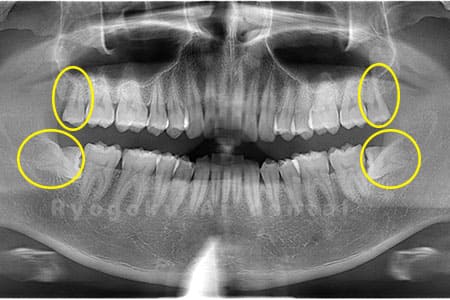

Case03

- 原因

- 上顎、下顎の親知らず

- 治療内容

- 上下4本の親知らずを抜歯したケースです。

<リスク・副作用>

手術後は痛み、腫れ、痺れなどの副作用が生じる場合があります。